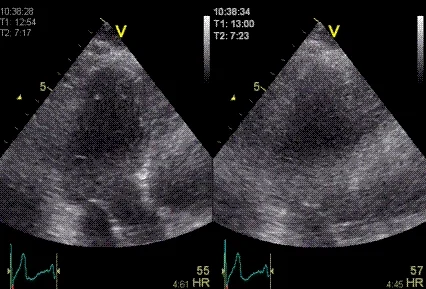

🫀 초음파검사

일반적인 경우 병원에서 복부 초음파 검사를 통해 태아의 심장 박동을 확인해요. 이때 태아 크기와 위치, 태반 상태, 양수량 등을 함께 살펴본답니다. 임신 중 실시하는 초음파검사는 태아와 산모에게 안전하니 걱정하지 않으셔도 돼요.👌🏻